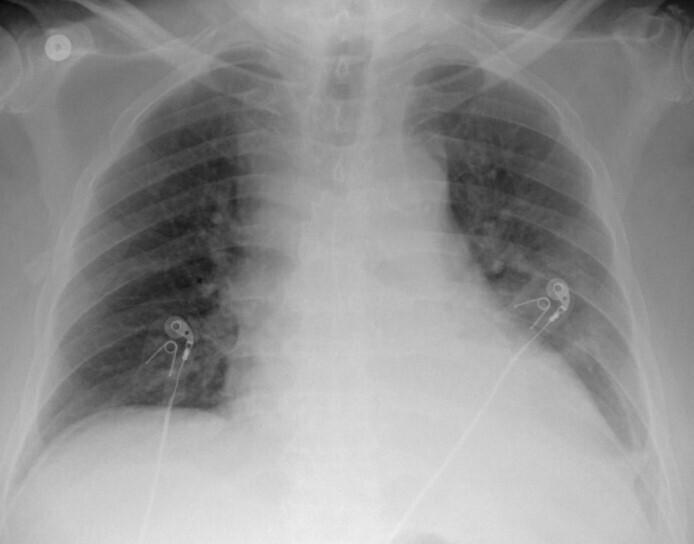

地诺单抗诱导的严重低钙血症继发难治性休克

Refractory Shock Secondary to Denosumab-induced Severe Hypocalcaemia.

Denosumab is one of the most commonly used antiresorptive drugs for osteoporosis treatment and the prevention of skeletal-related events in cancer patients. The purpose of this case report is to highlight potentially life-threatening severe hypocalcaemia as a side effect of denosumab complicated by refractory shock that failed to respond to medical management including intravenous calcium, vasopressors and inotropes in an elderly man with a history of prostatic cancer.

地诺单抗是治疗骨质疏松症和预防癌症患者骨骼相关事件最常用的抗吸收药物之一。本病例报告的目的是强调在一名有前列腺癌病史的老年男性中,地诺单抗作为一种副作用可能导致危及生命的严重低钙血症,并伴有难治性休克,对包括静脉补钙、血管加压药和正性肌力药在内的药物治疗无反应。